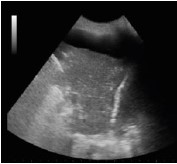

Assinale a opção que apresenta a imagem de ultrassonografia pulmonar compatível com a descrição do quadro acima.